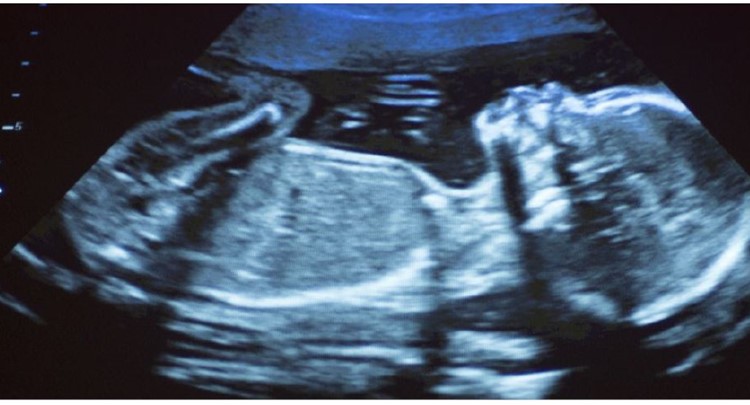

Research undertaken by scientists at Hasselt and Aberdeenuniversities reveals that traces of air pollution are present in the vital organs of unborn babies. Prof Tim Nawrot points to earlier research by his team that showed the presence of soot particles in all stages of pregnancy. The present research confirms the particles also enter the foetus’s organs. The soot particles in the air mainly originate from the burning of fossil fuels like diesel and heating fuel. In the past studies have shown the negative impact these particles can have on everybody’s health including that of the unborn.

Research conducted in Hasselt in 2019 revealed the presence of soot particles in the placenta during the early stages of pregnancy. “At twelve weeks we discovered soot particles on the mother’s side and on that of the foetus,” says Nawrot. Concentrations were highest on the foetus’s side. Researchers now wanted to establish the exact impact of soot particles in foetus development in the womb. The scientists discovered soot particles finding their way to the liver, the lungs and even the brain at a time when these vital organs are in full development. Prof Paul Fowler of Aberdeen University is particularly concerned about the presence of soot particles in developing brains. Exposure to air pollution during pregnancy has been linked to still and premature births, poor weight and disrupted brain development. The researchers say their work underpins the need to limit soot discharges because of the role it can play in the early stages of human development.